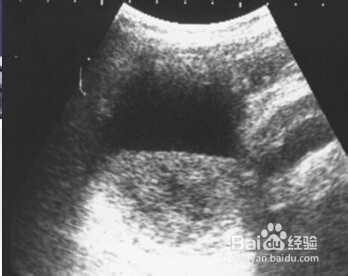

4、四:胆囊壁增厚及沉积物。